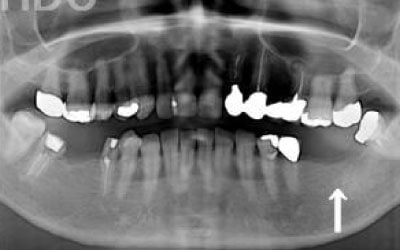

2 歯が傾いてくる、落ちてくる

歯はお互いに支え合ってバランスを取っています。ですので、歯が抜けるとその支えがなくなり、抜けた部分の隣の歯が倒れたり、上の歯が下に下がってくることがあります。